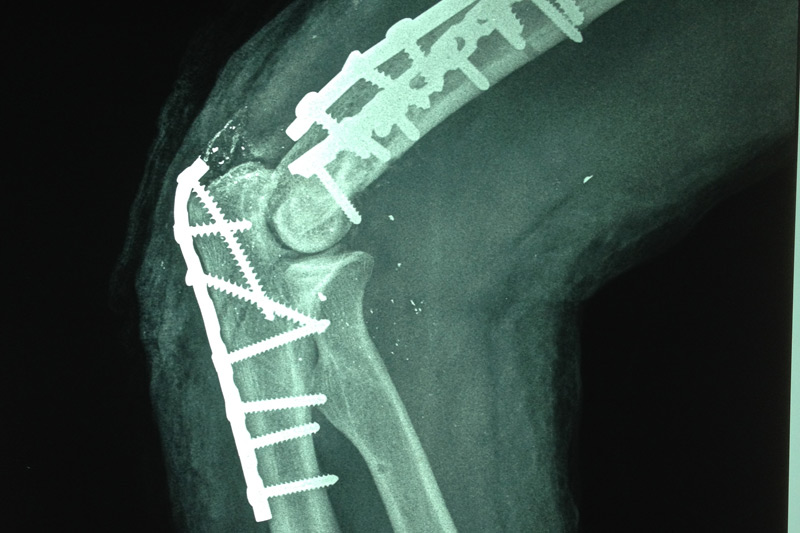

Dentro del avance en medicina se incluye la cirugía artroscópica, su característica es la mínima invasión, se realizan portales ( incisiones ) menores de 8 mm, por el cual se realizan cirugías ortopédicas con la finalidad de restaurar la congruencia articular, obteniendo excelentes resultados incluyendo ausencia de dolor y una pronta reincorporación a sus actividades cotidianas.